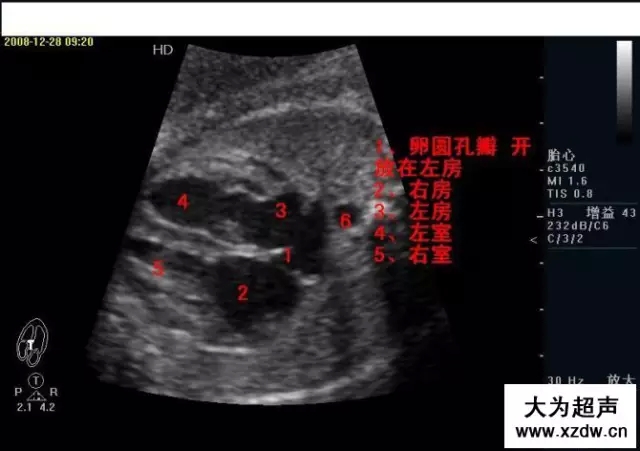

產科超聲正常圖片